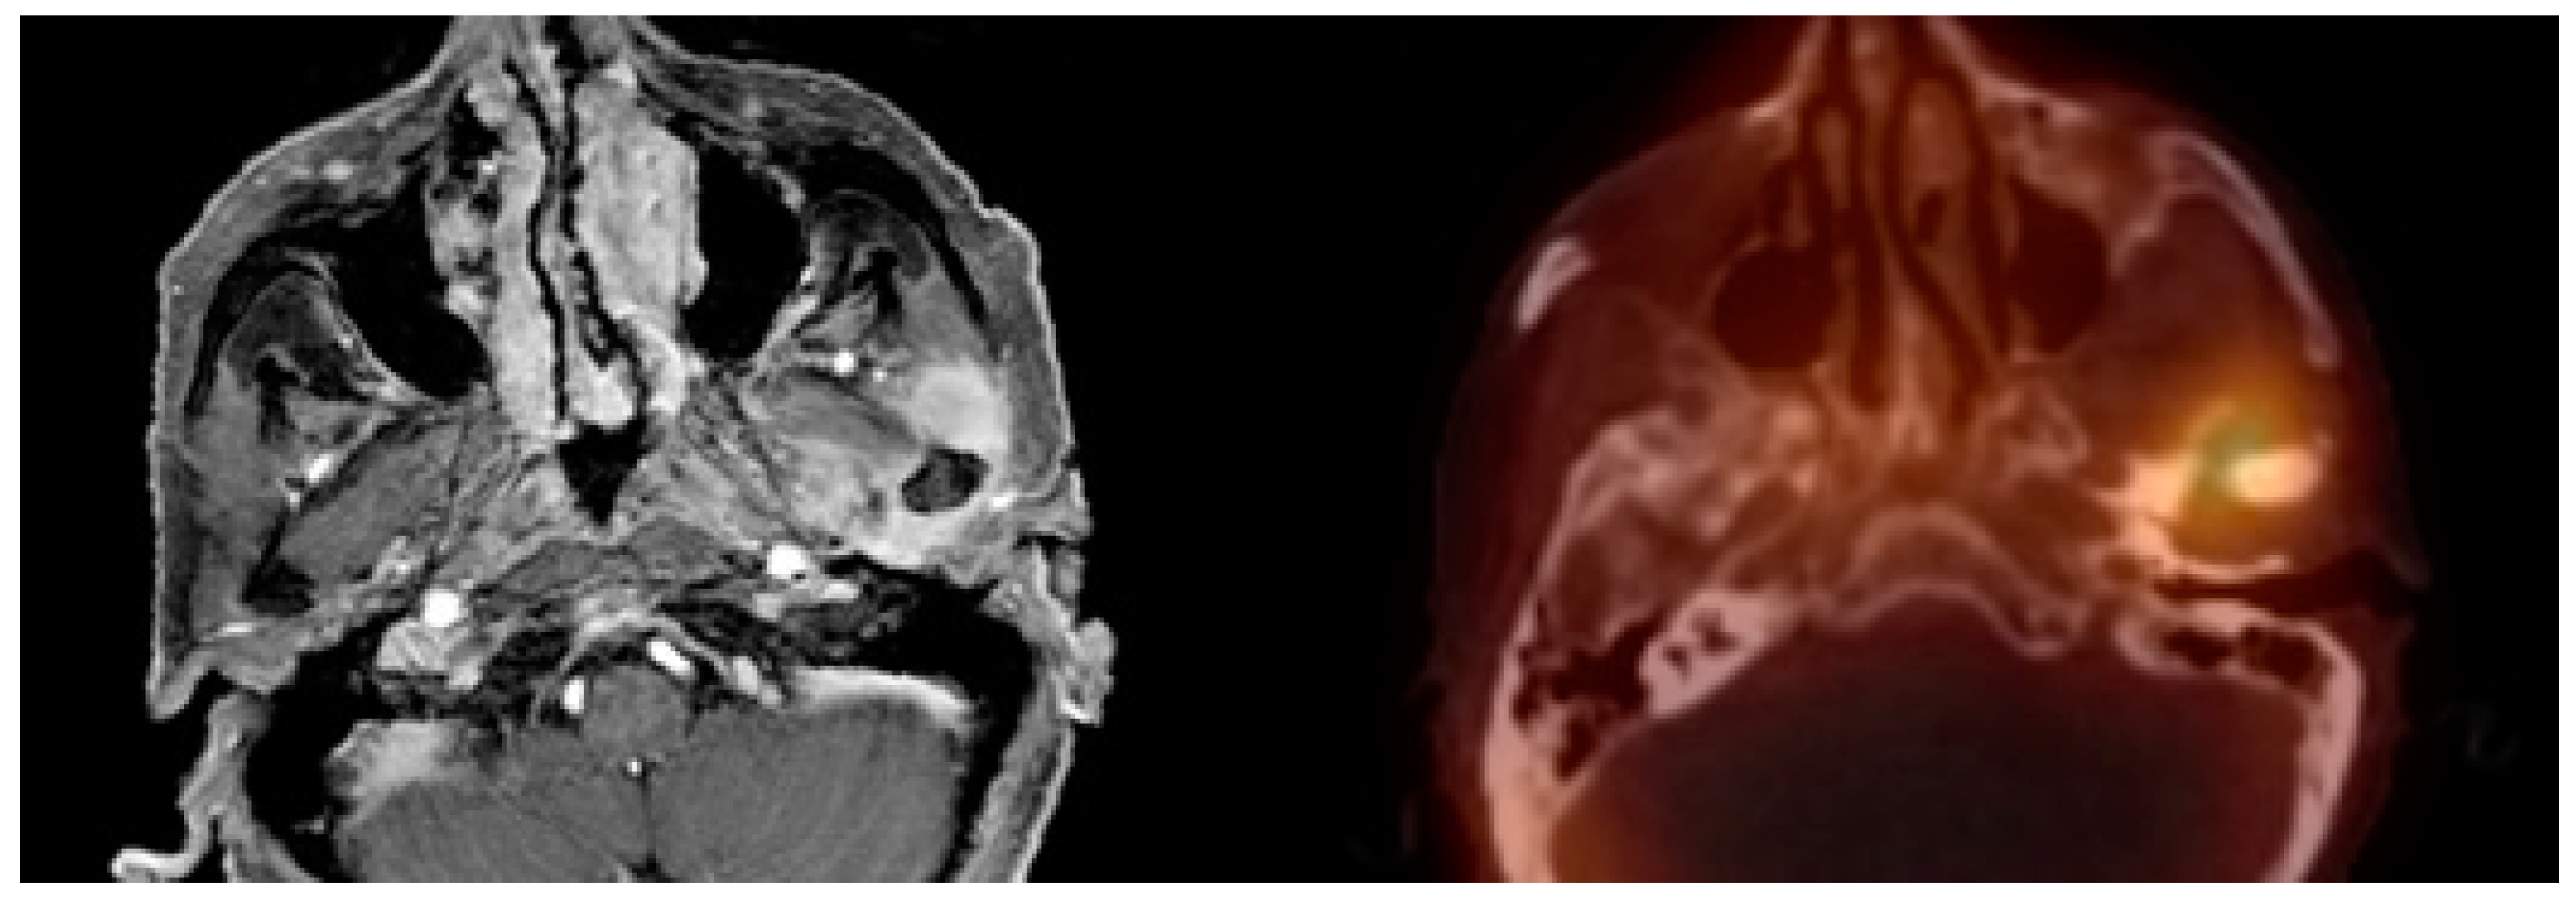

3. Results